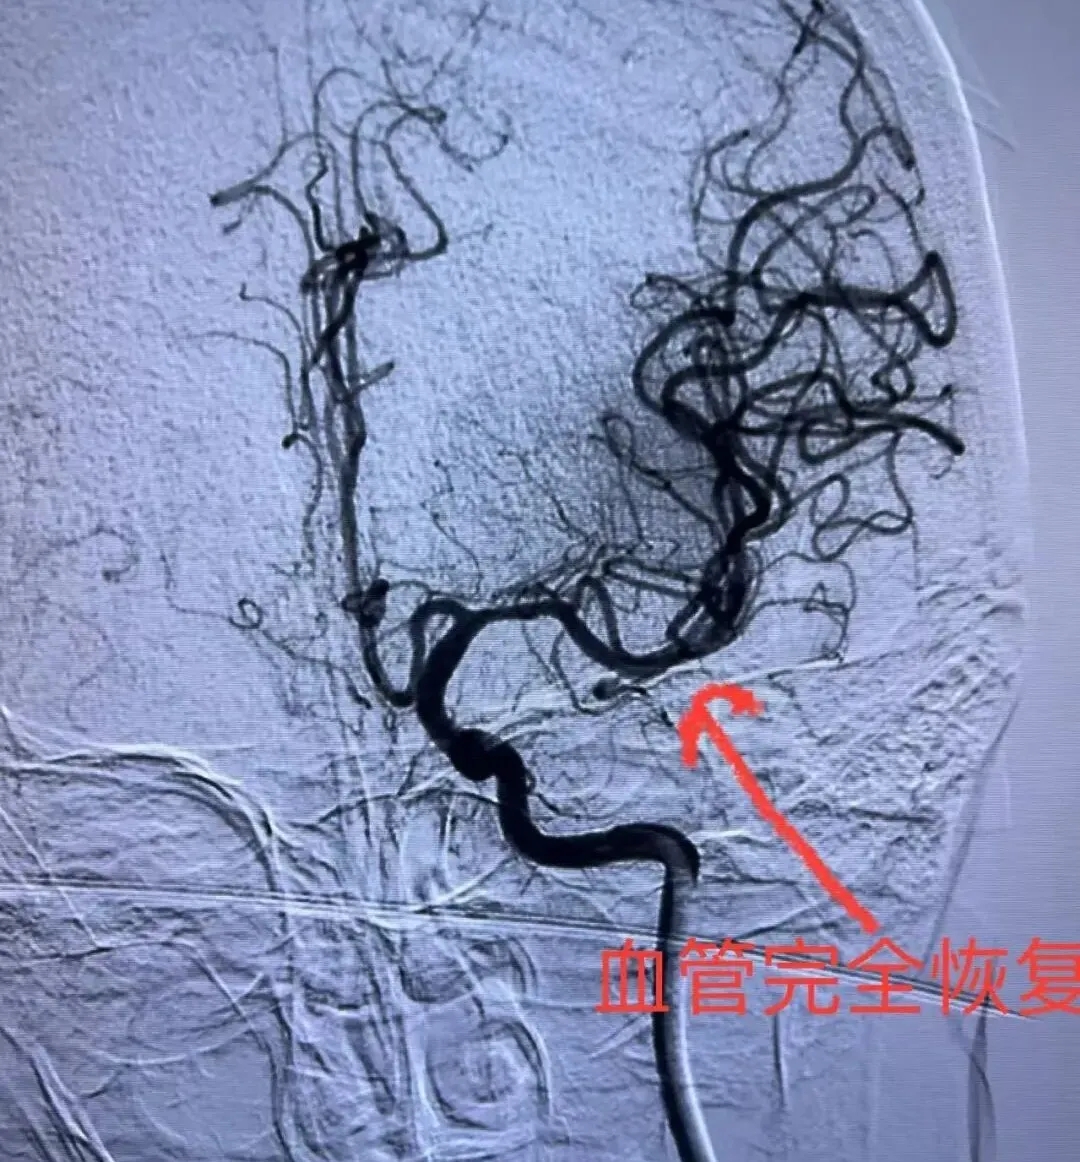

因大脑中动脉位置深、路径迂曲,且患者血管条件可能存在个体差异,此次取栓手术对医生的技术、经验及器械操控能力都是严峻考验。刘庆春副主任医师凭借丰富的经验,稳准快地建立通路,将微导丝、微导管巧妙通过迂曲的路径,导航至闭塞段。在DSA(数字减影血管造影)的实时引导下,取栓支架被精准释放于血栓部位,短暂等待后,通过牵拉将血栓顺利完整取出。复查造影显示,原先闭塞的大脑中动脉血流完全恢复(mTICI 3级再通),血流重建也标志着患者大脑功能的保护迎来了决定性转折。术后,于女士的意识状态逐渐好转,肢体肌力也开始改善,取得了远超预期的恢复。